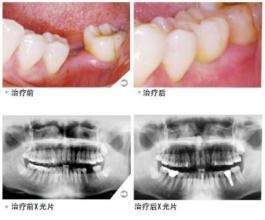

种植牙不同于固定义齿和假牙,不仅患者在使用以及体验上不同。对于医生以及的要求也颇高。大家在选择种牙前,需要对的技术以及医生多做了解。美奥口腔在种植牙上经验丰富技术过硬,下面就来具体的介绍一下,我们的专业种牙过程,希望对大家有帮助。>>点击在线咨询详情<<

1、口腔检查:在种植牙手术前,医生会对患者的口腔做一次检查,对于口腔环境不符合标准的会配套实施相关的手术。>>点击在线咨询详情<<

7、带上牙冠:种植钉与牙槽骨紧密愈合后,安装烤瓷牙冠后就完成了整个种植牙手术的全过程。综合来说,种植技术对于设备以及医生的专业技术的要求比较高,但是这也是保证种植修复效果的重要保障。>>点击在线咨询详情<<

南宁牙博士引进的即刻种植技术,利用手术方式和技术来完成种植牙过程,一般种植体植入手术只需要十几分钟即可以完成。创伤小,术后即可进食,几乎没有痛苦。种植牙对人体没有什么影响,广大美牙人士可以放心选择.>>点击在线咨询详情<<